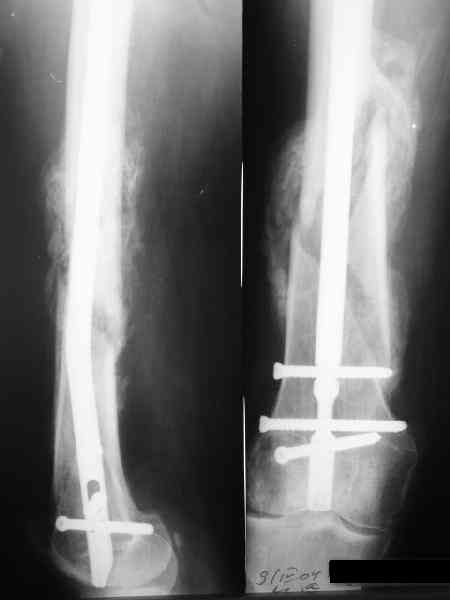

В приложении как раз видна эволюция использововшихся у нас большеберцовых гвоздей. Первый - дизайн как у UTN, второй - разнесены 45 градусные отверстия (зачем их вообще изначально так нелепо на одном уровне сделалм???), третий - убрано сиавшее лишним статическое отверстие, Herzog's bend перемещен более проксимально.

Забавненько смотрится... "век живи, век учись", как говорится. А чья мысль использовать блокируемые штифты для б/берцовой кости при переломах бедра? Такое встречалось где-то в литературе или это ваше ноу-хау?

Некоторые этот вариант воспринимают чуть ли не как покушение на святое, мол, если "Дарованная Нам Свыше Оригинальная Методика" не предусматривает такое, то это ересь и крамола. Хотя тут все самоочевидно - необходимый результат достигается.

Насколько я помню, мы использовали этот вариант после знакомства с гвоздями SIGN, которые вообще одинаковые для бедра и голени, и дизайн у них большеберцовый.